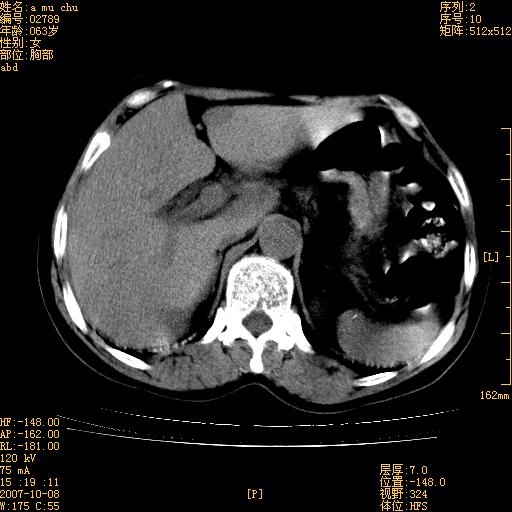

以下是引用王维浦在2007-10-17 21:02:00的发言:[br]胆囊增大,囊壁明显不规则增厚,邻近肝组织浸润,肝内外胆管无扩张。诊断:胆囊ca;[br]胰头软组织肿块影,考虑是由转移肿大的胰后淋巴结、没有肠道准备的十二指肠及胰头共同形成。[br]

以下是引用zhangzexing在2007-10-18 7:13:00的发言:[br]支持胰头占位,慢性胆囊炎. 2.肝左叶前外侧段占位,血管瘤?建议增强

以下是引用影像实习生在2007-10-17 19:49:00的发言:[br]支持胰头占位,慢性胆囊炎. 2.肝左叶前外侧段占位,血管瘤?建议增强.

以下是引用刘振江在2007-10-17 19:42:00的发言:[br]没有增强,胰头癌?胆囊及肝左叶占位?